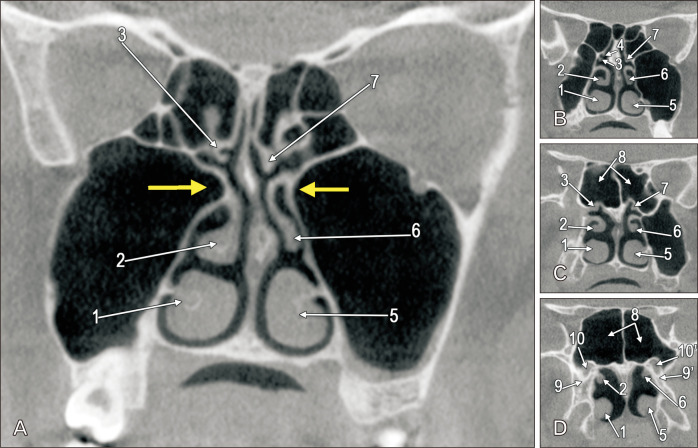

Pneumatisation of the maxillary sinus (MS) is variable. The archived cone-beam computed tomography file of a 54-year-old female was retrospectively evaluated anatomically. Nasal or retrobullar recesses of the MSs (NRMS) were found. The MSs were bicameral. NRMSs extended from the postero-lateral chambers of the MSs into the lateral nasal walls. The right NRMS was reached superior to the middle turbinate and the ethmoidal bulla was applied on its anterior side. The left NRMS had two medial pouch-like ends, one beneath the ethmoidal bulla and the other on the anterior side of the basal lamella of the middle turbinate. Additional anatomical findings were the uncinate bulla, infraorbital recesses of the MS, maxillary recess of the sphenoidal sinus, and atypical posterior insertions of the superior nasal turbinates, maxillo-ethmoido-sphenoidal and ethmoido-sphenoidal. The NRMS is a novel finding and could lead to erroneous endoscopic corridors if not documented before the interventions.

上颌窦(MS)的充气情况多种多样。我们对一名 54 岁女性的锥形束计算机断层扫描档案进行了回顾性解剖评估。发现了上颌窦的鼻腔或髓后凹陷(NRMS)。多发性硬化症为双侧。NRMS 从 MS 的后外侧腔延伸至鼻侧壁。右侧 NRMS 位于中鼻甲上方,乙状鼓室位于其前侧。左侧 NRMS 有两个内侧袋状末端,一个位于乙状鼓室下方,另一个位于中鼻甲基底层前侧。其他的解剖学发现包括钩状鼓室、MS 的眶下凹陷、蝶窦的上颌凹陷以及上鼻甲、上颌-乙状-蝶窦和乙状-蝶窦的非典型后方插入。NRMS 是一项新发现,如果不在干预前记录下来,可能会导致错误的内窥镜走廊。